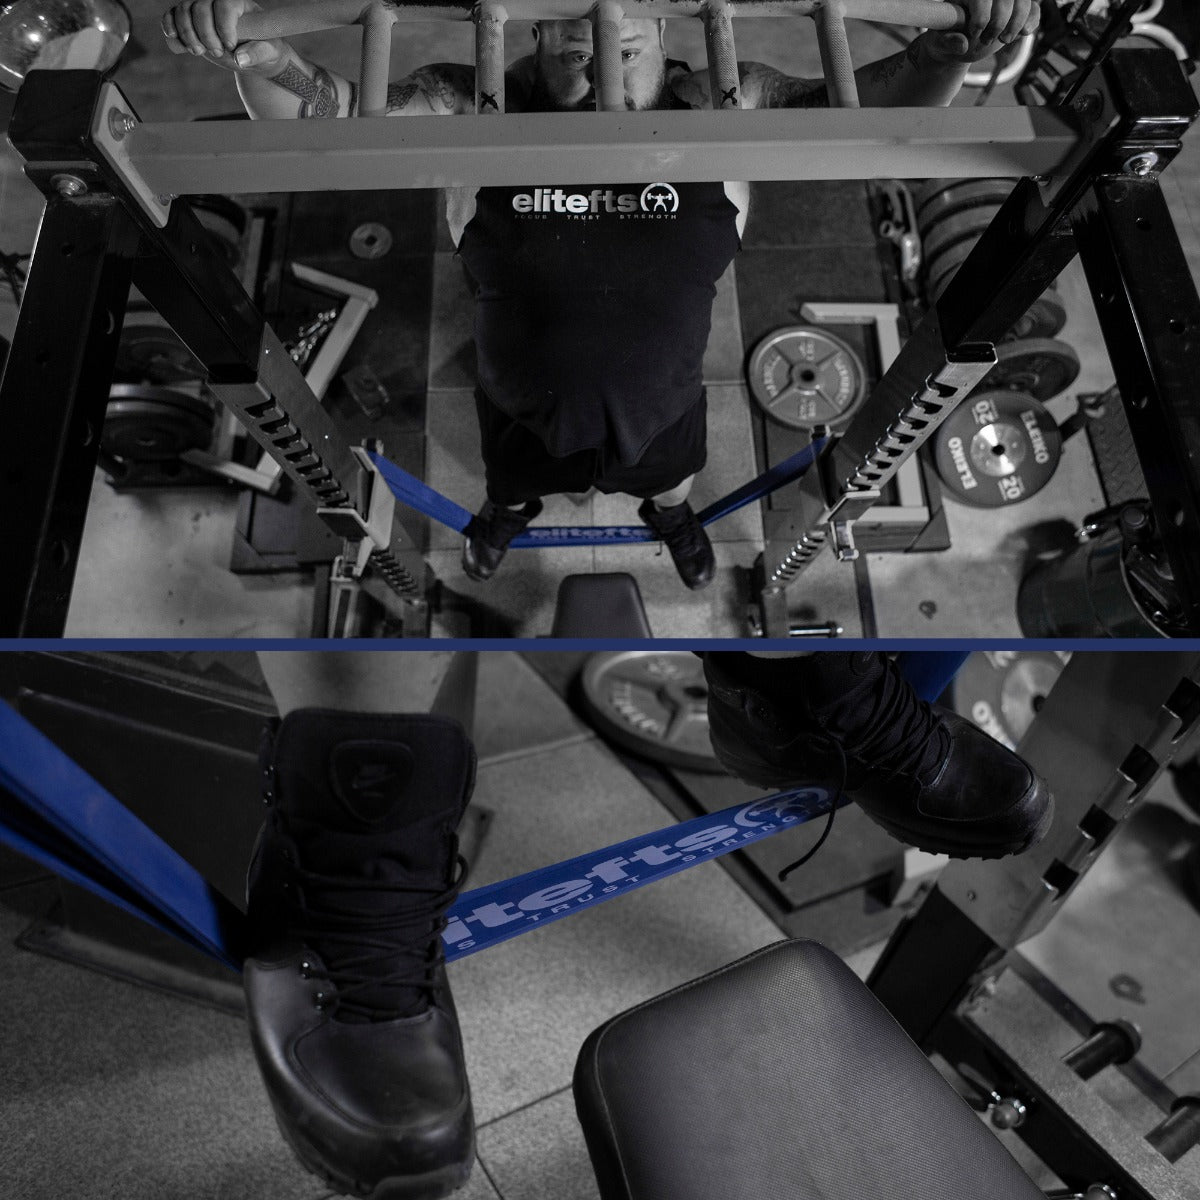

Well, at Synergy Strength Systems, we have a kid named Jordan who has this condition, and he comes in three days a week to train. When Jordan came in, he didn’t have a clue what to do. I watched him come in day after day and struggle with his routine. One day I offered him a few tips on his lower body training and, surprisingly, he listened. Once I knew that he was open to getting better and stronger, we used a slightly modified version of 5/3/1 (I hope Jim Wendler doesn’t come and crush me for doing that). Instead of using the protocol where you progress from week to week, I had him stick with three sets of five for the squat and deadlift for five weeks. We also made sure to use the assistance exercises that are prescribed. The reason I did this was because he informed me that if he goes too hard on the training, it may induce an attack, which would leave him bedridden for a few days, something we both wanted to avoid.Weightlifting

Jordan is one of those rare breeds of individuals who doesn’t use his illness as an excuse to be lazy and not do anything. Instead, he's in the process of starting an organization to raise awareness of the disease at historically black colleges and universities (HBCU). He's also a biology major and wants to be a doctor. Below are a few videos of Jordan training. Check them out. This kid is strong and getting stronger thanks to determination and the will not to quit or be held back! Oh, he's only 130 pounds, too! Jordan deadlifting Jordan squatting on thesafety squat yoke bar